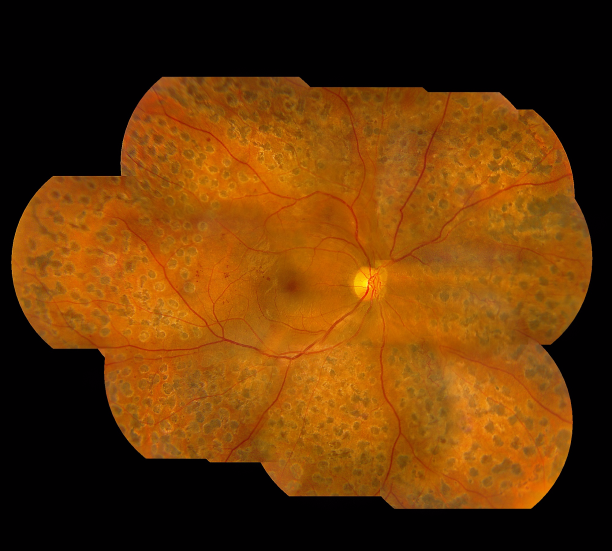

而我们的视网膜布满了大量的微丝血管,如果血糖长期不稳定,有可能导致视网膜血管内皮细胞遭到破坏,进而引发一系列的眼底病变,如微血管瘤、糖尿黄斑水肿、视网膜新生血管,甚至视网膜脱落或青光眼,这些眼疾若未及时治疗,严重情况下有失明的危险。

除了定期检查,糖尿病患者也可以通过自身的一些症状来预知糖网病的“侵袭”。由于糖尿病视网膜病变主要有三种形式可以对视力造成严重影响,它们分别是黄斑水肿、眼内出血以及视网膜脱离,所以糖尿病患者如果出现了以下症状,就需要警惕了: